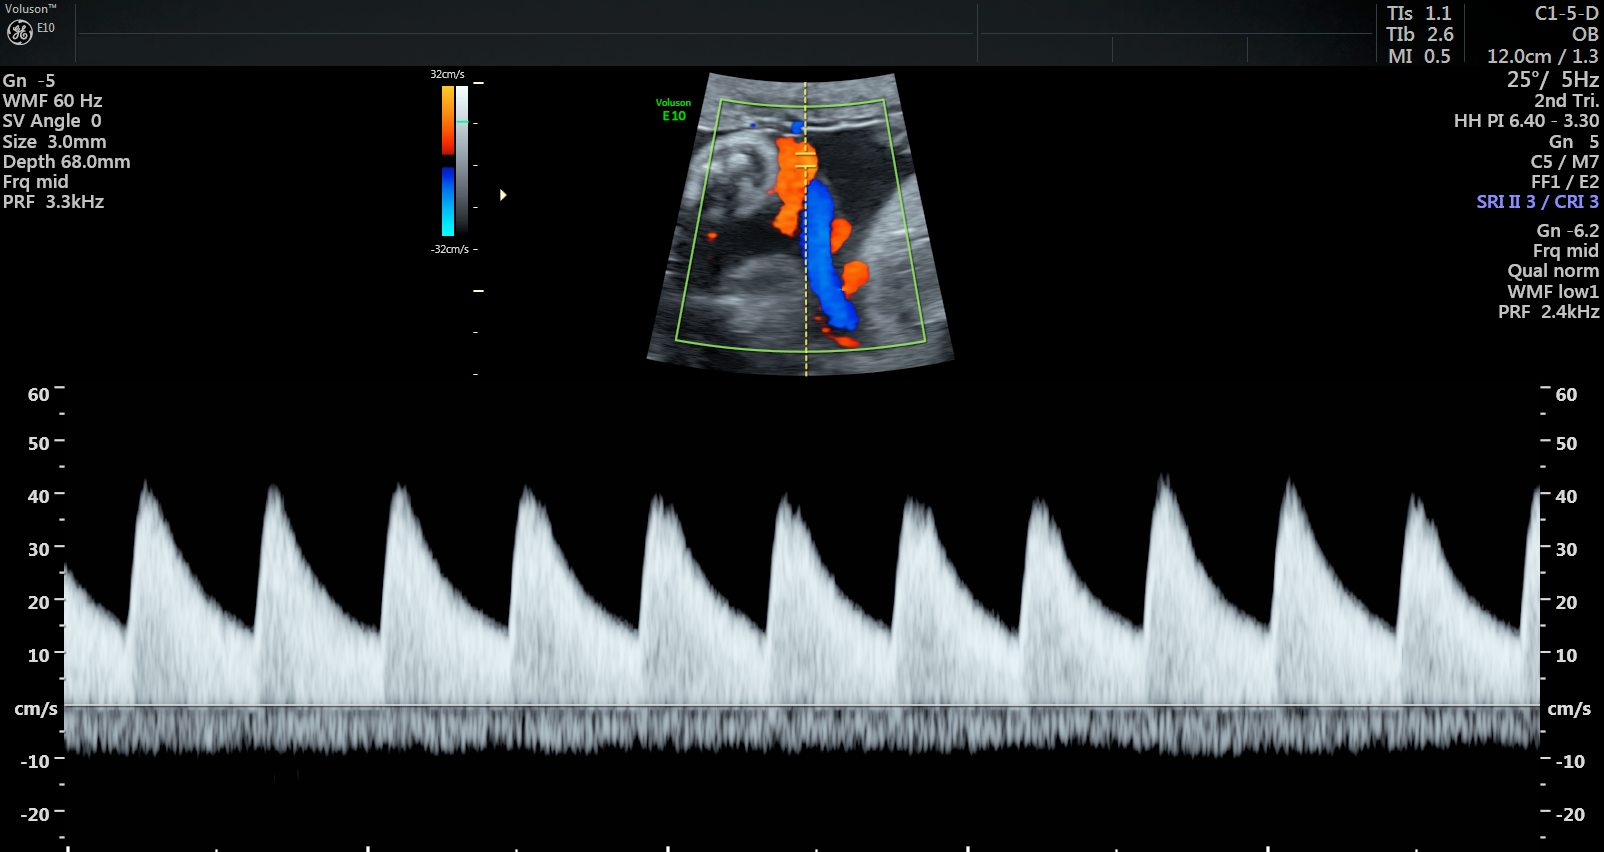

Currently, standard-of-care ultrasound scans measure blood flow at one point in the umbilical cord. The technique developed by Sled and his collaborators takes two measurements – one at the fetal end of the umbilical cord and one at the placental end. Sled says recording both measurements gives a much more accurate picture of the way blood is travelling through the umbilical cord.

“By looking at both measurements and the physics of how blood travels, we can get insight into how some of the finest blood vessels in the placenta are organized. The information this can provide to physicians is invaluable,” says Sled, who is also the Director of the Mouse Imaging Centre and a Professor and Vice-Chair in the Department of Medical Biophysics at the University of Toronto.

Animation showing where the new ultrasound technique measures blood flow along the umbilical cord. One measurement is taken at the fetal end and one is taken at the placental end.